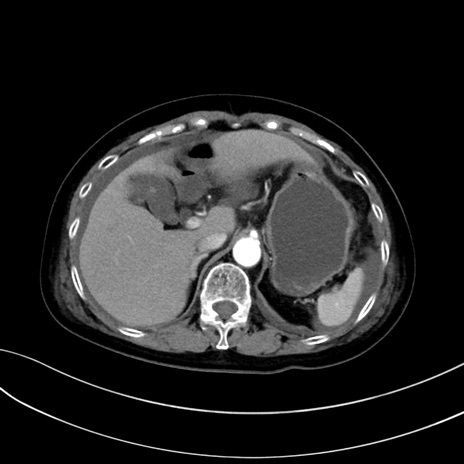

症例13 CT(横断像)1日半後